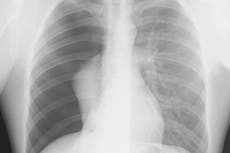

The coronavirus targets the lungs foremost, but also the kidneys, liver and blood vessels. Still, about half of patients report neurological symptoms, including headaches, confusion and delirium, suggesting the virus may also attack the brain.